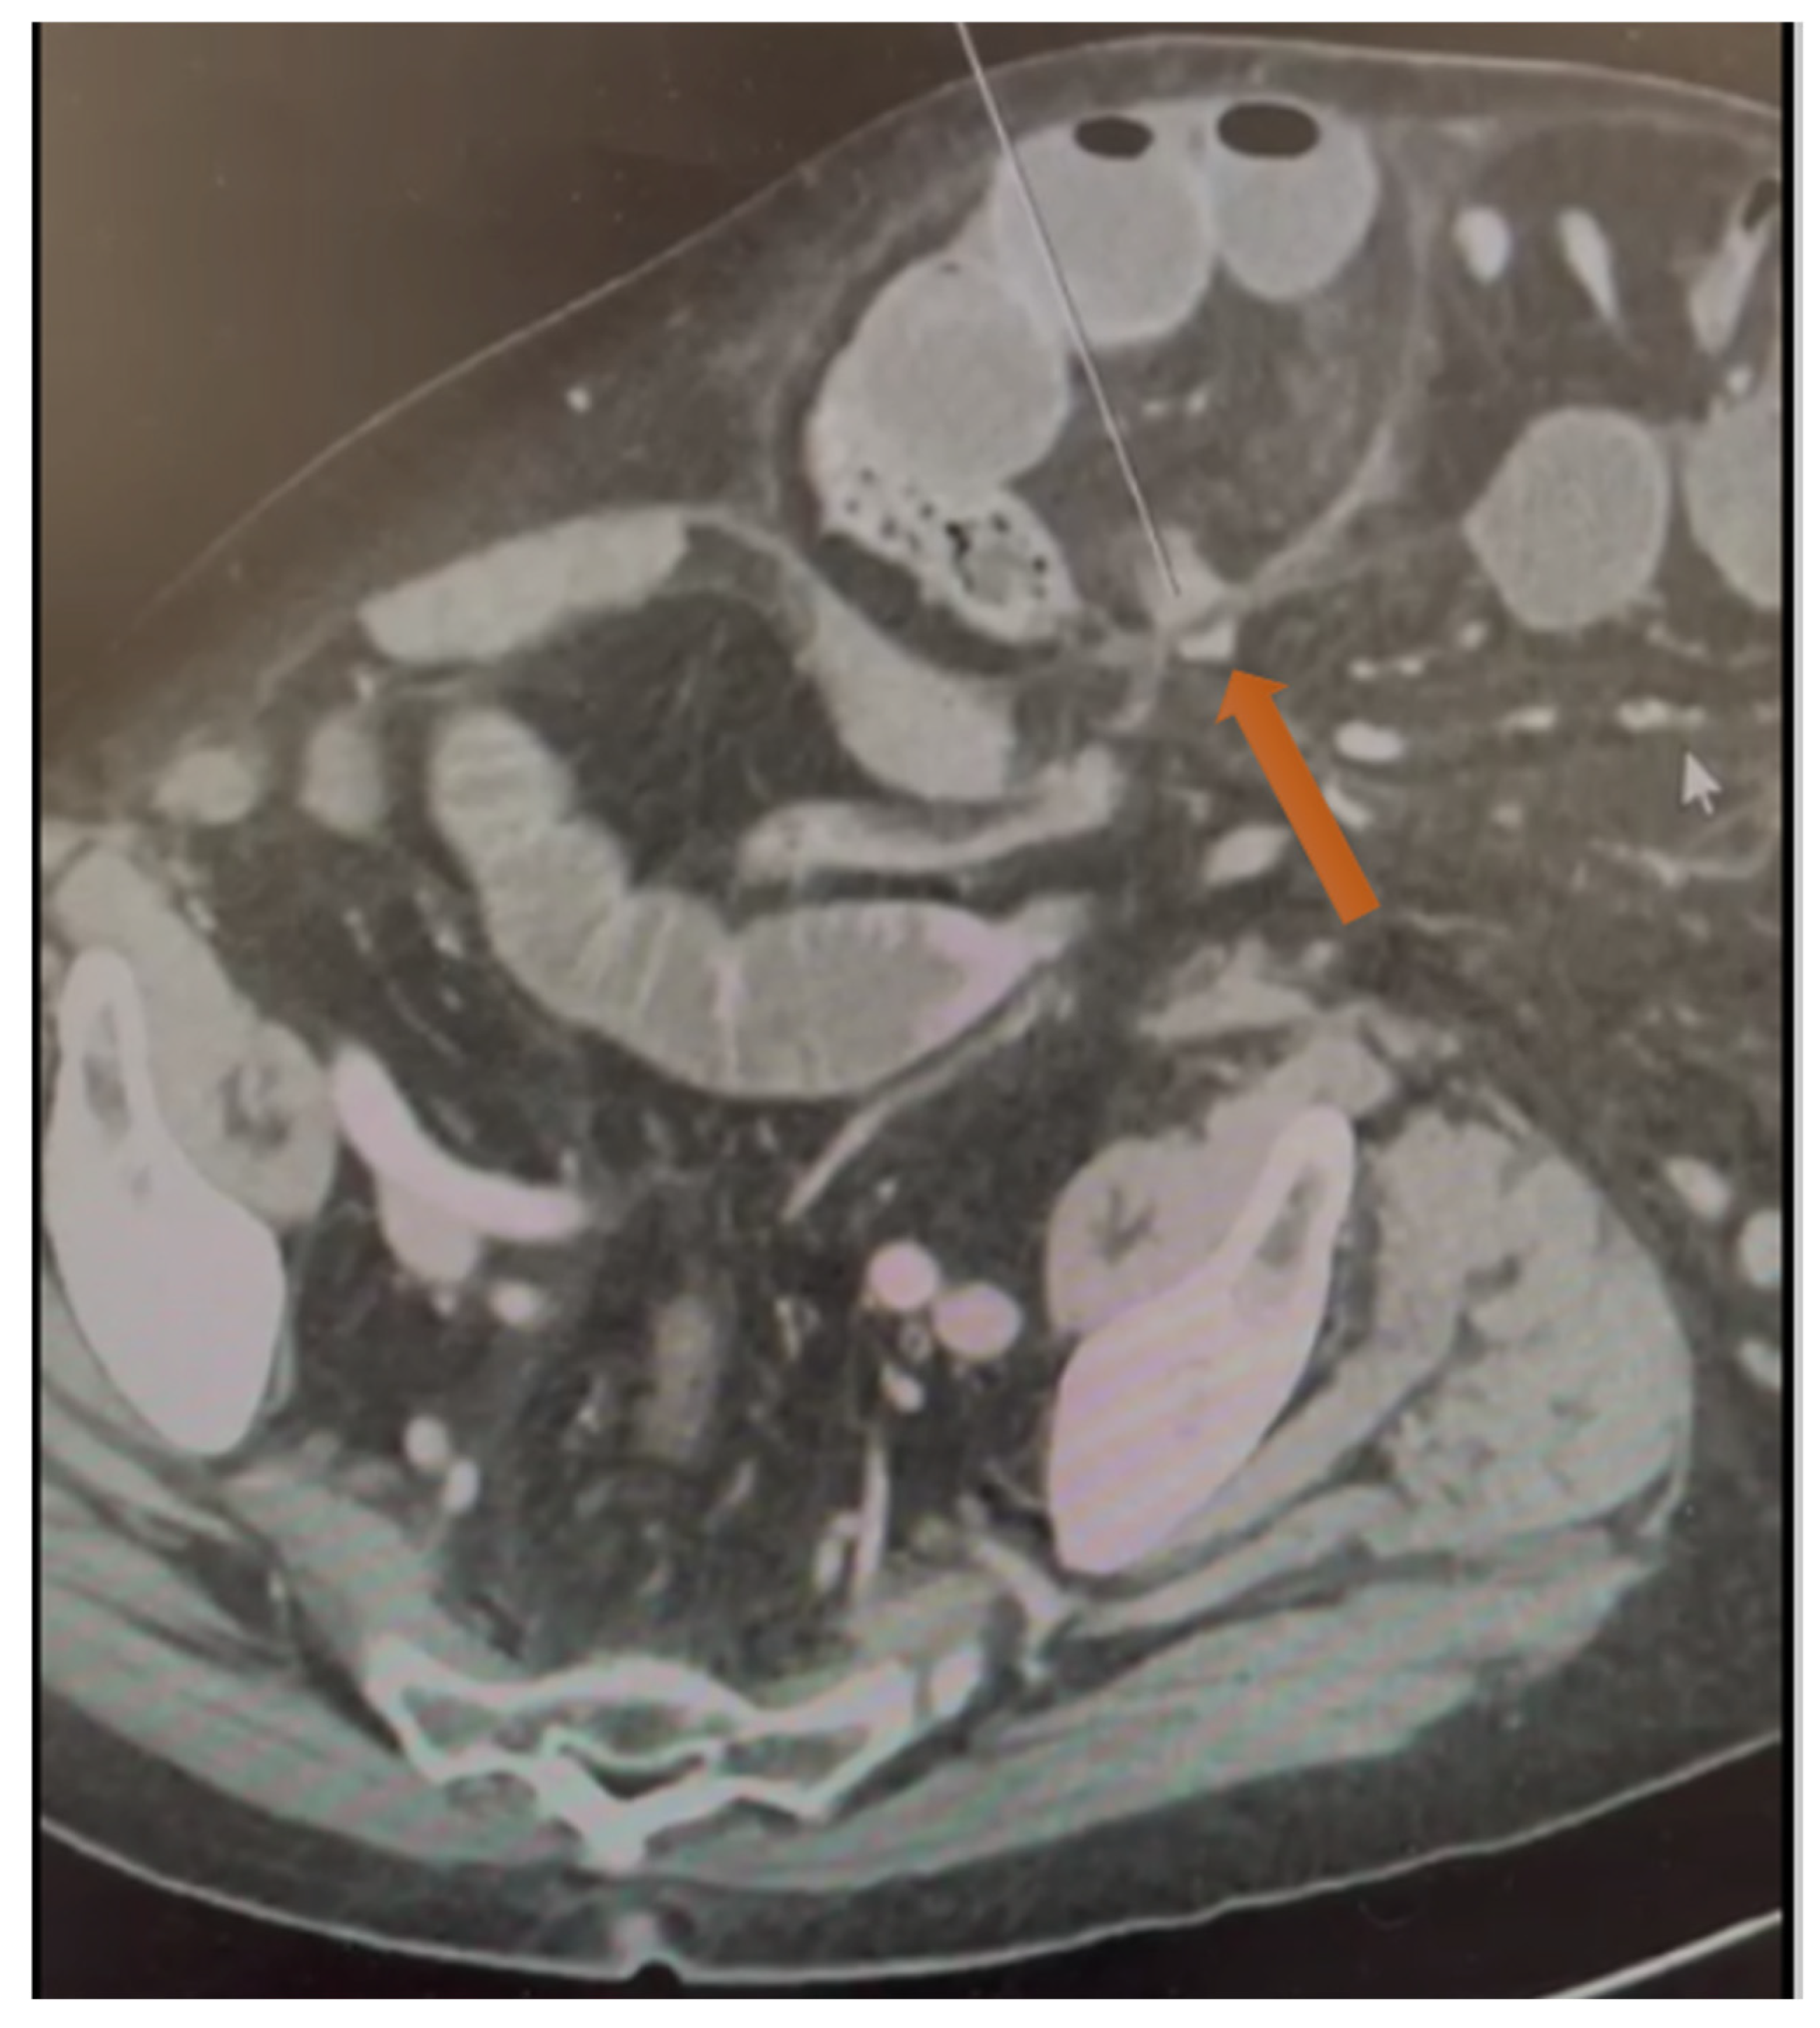

Figure 2.

Axial CT scan demonstrating intrasaccular septation (see the orange arrow) that explains the internal compartmentalization and strangulation within this chronic irreducible incisional hernia.